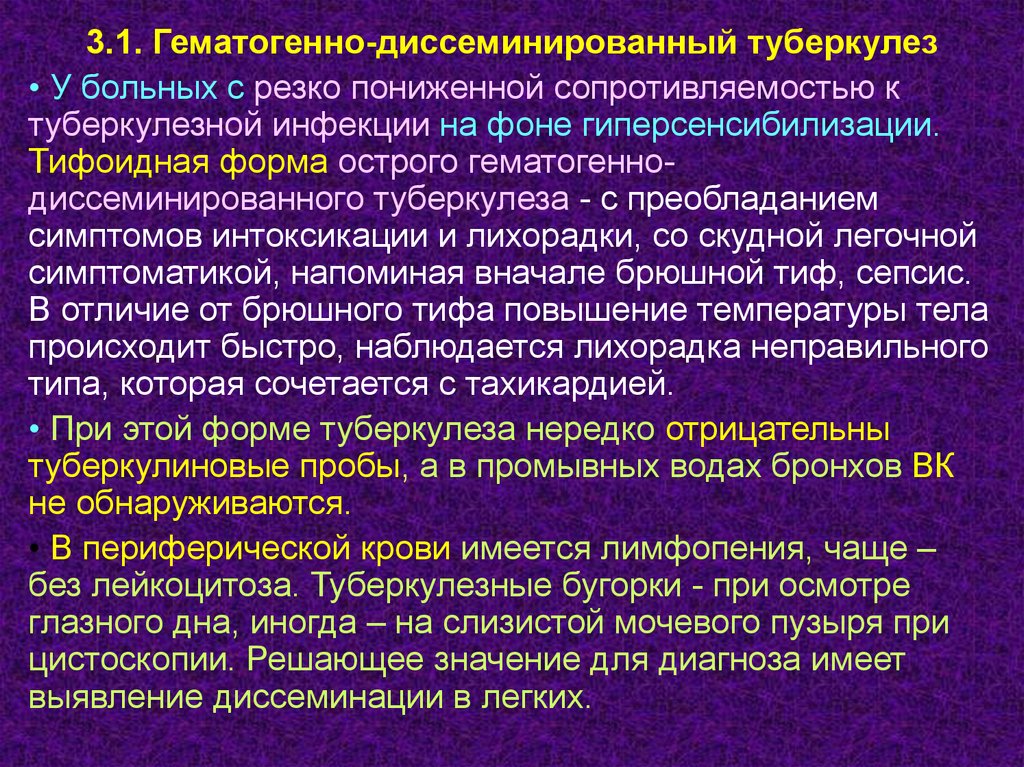

В клинической картине острого гематогенно диссеминированного туберкулеза преобладает